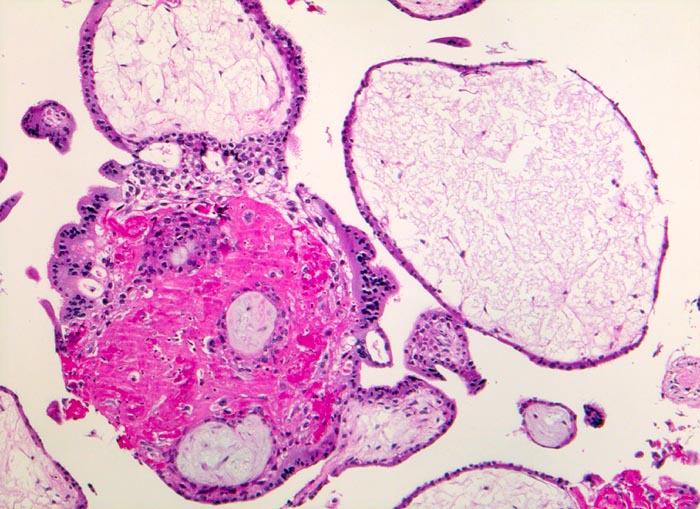

Chromosomenaberrationen verursachen nicht nur beim Feten, sondern auch an der Chorionzotte morphologisch fassbare Entwicklungsstörungen: mangelnde Verzweigungen, wandernde Trophoblastzellen im Stroma, mangelhafte Vaskularisation, hydropische Alteration des Stromas und herdförmige Atrophie oder auch Hyperplasie des Trophoblasten sind typische Befunde bei einer Chromosomenaberration. Aborte mit Triploidie zeigen in der grossen Mehrzahl das Bild einer Partialmole. Eine Tetraploidie kann das Bild einer Windmole (=Windei), einer Embryonalmole oder seltener einer Partialmole verursachen. Autosomale Trisomien können ebenfalls als Windmole oder als Embryonalmole imponieren. In nur etwa 25% aller Spontanaborte sind bei der pathomorphologischen Untersuchung ein Embryo, Embryofragmente oder ein Nabelschnuranteil nachweisbar. Die morphologische Untersuchung des Abortmaterials stellt eine wichtige Ergänzung zu den klinischen Befunden dar.

• Vergrösserte Plazentarzotten mit hydropischem Zottenstroma.

• Vereinzelt Zytotrophoblasteinschlüsse im Stroma.

• Vorwiegend einschichtiges Zytotrophoblastepithel ohne Atypien und mehrkerniger Synzytiotrophoblast. Physiologische polare Trophoblastproliferate.